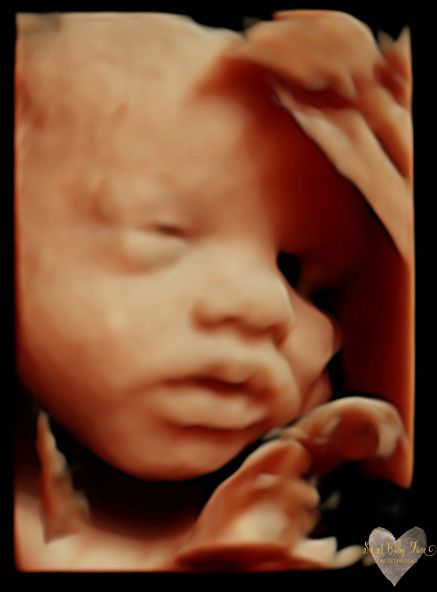

3D/4D/5D Ultrasound Gallery

Take a peek at our Photo Gallery. All of our 2D, 3D, 4D, HD elective ultrasound images are truly ours. They come directly off our machine from our highly trained staff. We can start getting great 3D/4D images as early as 10 weeks!